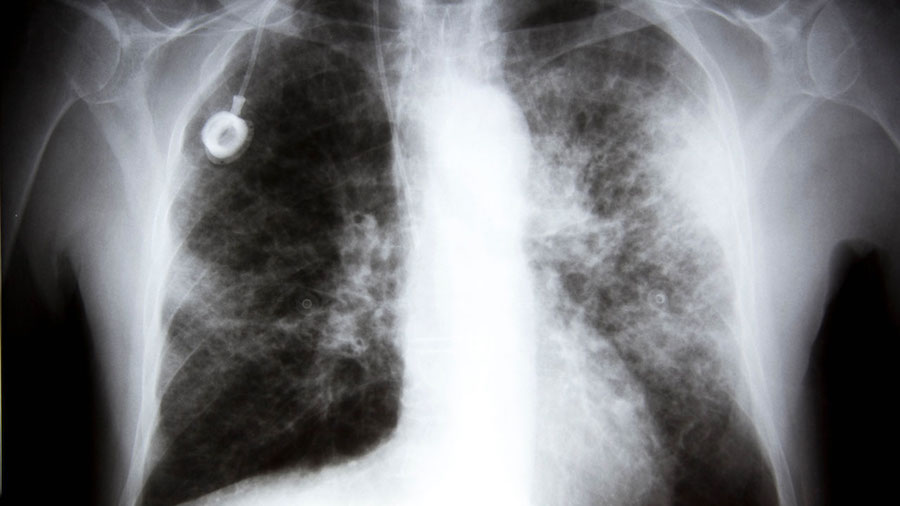

Specifically, they looked at the relationship of breast cancer to the closest organs, the lungs, when treated with paclitaxel.

Lead researcher Tsonwin Hai explained that the gene seems to do two destructive things: distribute cancer cells around the lungs, and “fertilize” the area to make the cells more likely to survive and thrive.

It seems to set off a molecular chain reaction that makes the lung environment much more conducive to cancer.